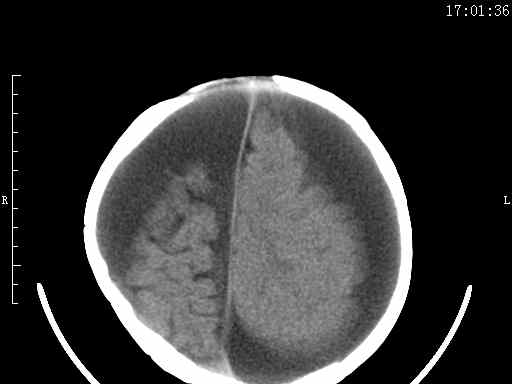

以下是引用余辉在2009-5-30 17:43:00的发言:[br]外围性脑积水在蛛网膜下腔,这个不像,双侧客部液区增宽,内见对称性弧形线状高密度影,边缘清晰锐利,右侧后端终止于冠状缝,左侧终止于人字缝,应该是硬脑膜.双侧硬膜下液区增宽,脑皮质受压变平,脑沟裂无显著增宽,考虑1双侧额颞顶部慢性硬膜外血肿伴硬膜下积液或慢性血肿2双侧慢性硬膜下积液伴硬脑膜剥离并有交通积液(反正考虑硬膜下及硬膜外的慢性血肿或积液)